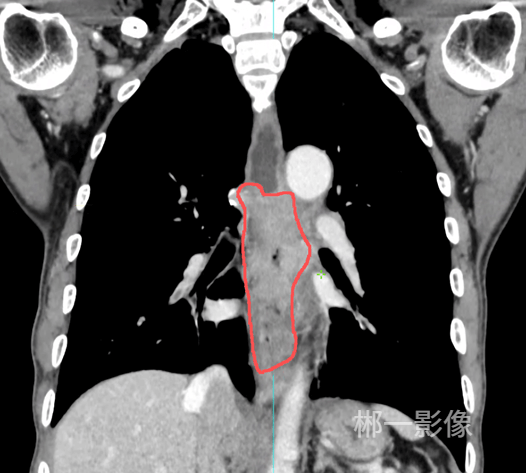

随后再通过CT扫描提供3D的全息地图,它能清晰勾勒出胃壁与腹壁最贴合的那个安全窗口,让医生能避开所有危险,选中那条唯一的最佳路径。

第一步,让胃部充盈起来,长期无法进食导致胃腔完全皱缩,无法获取足够的操作空间。于是在DSA的监视下,通过预先建立的通道,向王老的胃里注入了600ml空气。原本干瘪的胃腔像一个慢慢吹起的气球,稳稳地贴住了前腹壁。把游移不定的移动靶,变成了一个轮廓清晰的固定靶。

第二步,固定胃壁。病人被平稳转移到CT机上,扫描确认后,朱柏霖医生使用造瘘套件中的巧妙装置,在选定的穿刺点周围,像打两颗精密的膨胀螺丝一样,将胃壁和腹壁轻柔而牢固地缝合在一起。

最后,用影像确认胜利。再次扫描CT,屏幕上清晰显示:造瘘管头端完美位于胃腔中心。手术顺利完成,留下的创口,仅有一个不大的针眼。而王老的腹壁上,则多了一根柔软的管子,对他而言是重新接通的命脉,一两天后王老就能通过这根管子正常的进食食物。